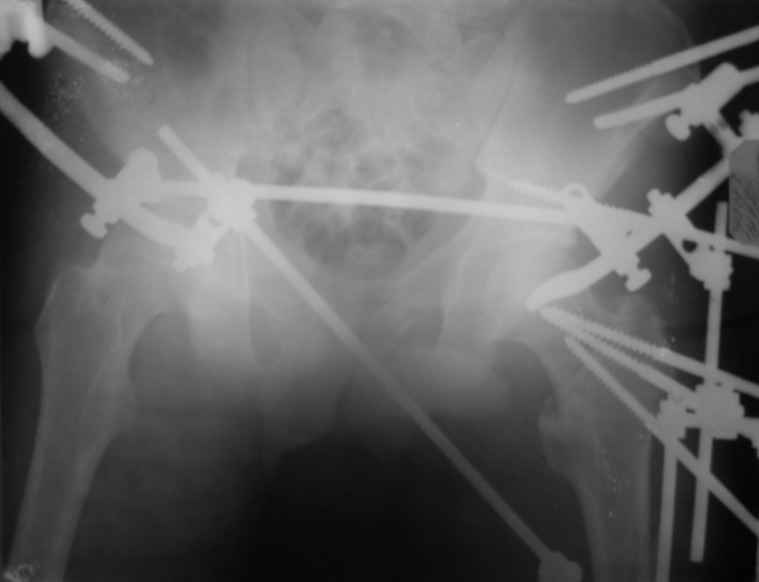

Вот снимки по свежей ситуации, парень 19 лет, длинный оскольчатый перелом бедра от шейки до в-с/3. давно уже ходит на своих ногах.

Делалось не мной (ассистировал), я на тазах "пока ещё не волшебник, а только учусь"

Представленные Вами рентгенограммы действительно являются примером качественной фиксации спице-стержневым аппаратом. Они, как ни что другое, многое иллюстрируют.

Кроме того, было бы ошибкой ставить знак равенства между нашим и Вашим пациентами. Они не только не похожи, разница между ними просто огромная. Говорю это не для того, чтобы задеть Вас или обидеть. Ни в коем случае. Просто теперь я понимаю, что Ваше мнением строится на простом преломлении Ваших подходов к лечению пациентов со свежими переломами, на ситуацию, абсолютно несопоставимую, подобную нашей.

Готов поспорить, не так уж огромна разница. Я вполне понимаю, что фиксация свежего отломка у 19-летнего парня и чего там осталось от головки-шейки-вертелов у вашего немолодого пациента - это не одно и то же. Но я продолжаю настаивать на том, что вы далеко не исчерпали возможности данного метода. А то, что вся ситуация происходит на фоне гнойной раны чуть ли не в самом очаге - вообще для меня делает непонятой дискуссию о выборе метода, метод выбора уже применяется, и даже успешно.

Если вернуться обратно к разнице - и там, и там главное что нужно пациенту после репозиции - качественная стабильная фиксация. Раз есть гной - значит, внеочаговая (так уж ортодоксально я обучен), и даже если существуют крутые технологии по погружному остеосинтезу на фоне гнойных проблем - тем не менее, зачем идти заведомо более сложным и затратным путём? Кроме того, зачем придумывать спейсер, когда вон какая мозоль и оссификаты, там есть чему срастись и так.

Компоновку данного аппарата, в котором дистальный отломок фиксирован лишь на дистальном уровне, а проксимальный вообще сам по себе никак, только через бывший сустав, назвать стабильной никак нельзя. Нет стабильности - нет нормального заживления, но есть осложнения, надеюсь, это-то можно экстраполировать на вашего больного?

ну и маленькая поправочка, в нашем аппарате нет спиц.